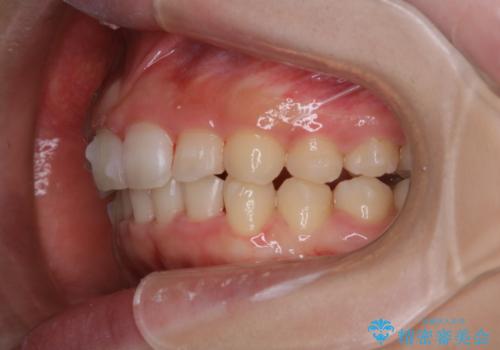

インビザライン中にステインの除去

- インビザラインでのマウスピース矯正中の方で、歯の表面のステインをきれいに取りたいとのことでした。PMTC60分コースを行いました。

PMTC(保険外治療)は、毎日の歯磨きで落としきれない汚れや、コーヒ、紅茶・タバコのヤニなどの着色も除去します。目には見えない歯と歯の間・歯肉の境目・インビザライン中はアタッチメント周囲などに残っているプラーク(歯垢)もしっかり取り除きます。PMTCでは専門的な機械や材料を使用して、徹底的に汚れを除去するため、虫歯・歯周病・口臭予防などにつながります。